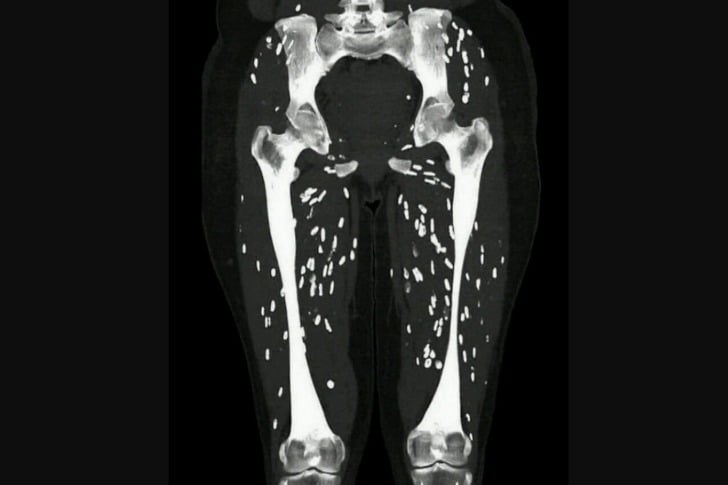

#15 Cysticercose musculaire. Il s’agit de larves de ténia dans le tissu musculaire.

Le patient présente une faiblesse et des douleurs musculaires.